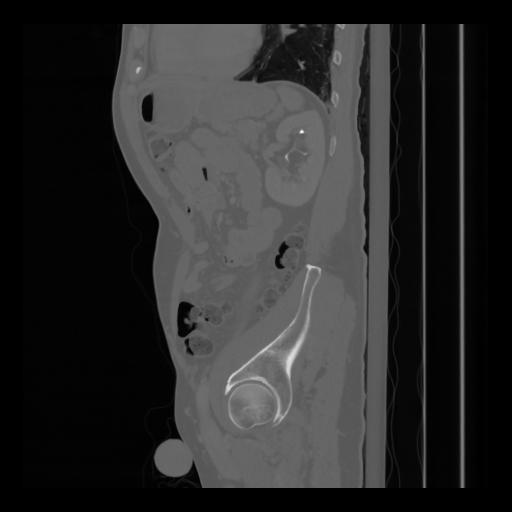

36 CUERPO,CE,Sagittal,3.000,CUERPO,Sagittal,